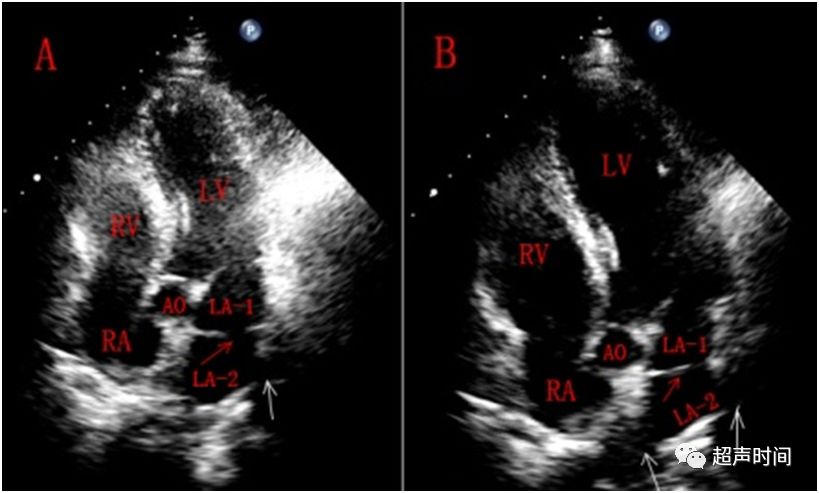

图 1 心尖五腔心切面。左心房内见隔膜样回声(红色箭头),经左心房外侧壁至房间隔中部,将左心房分为两个心腔,隔膜中央回声中断(红色箭头),似见三支肺静脉(白色箭头)开口于副房(LA-2)

图 2 剑下两腔心切面。左心房内见隔膜样回声(红色箭头),经左心房外侧壁至房间隔中部,将左心房分为两个心腔,隔膜中央回声中断(红色箭头)